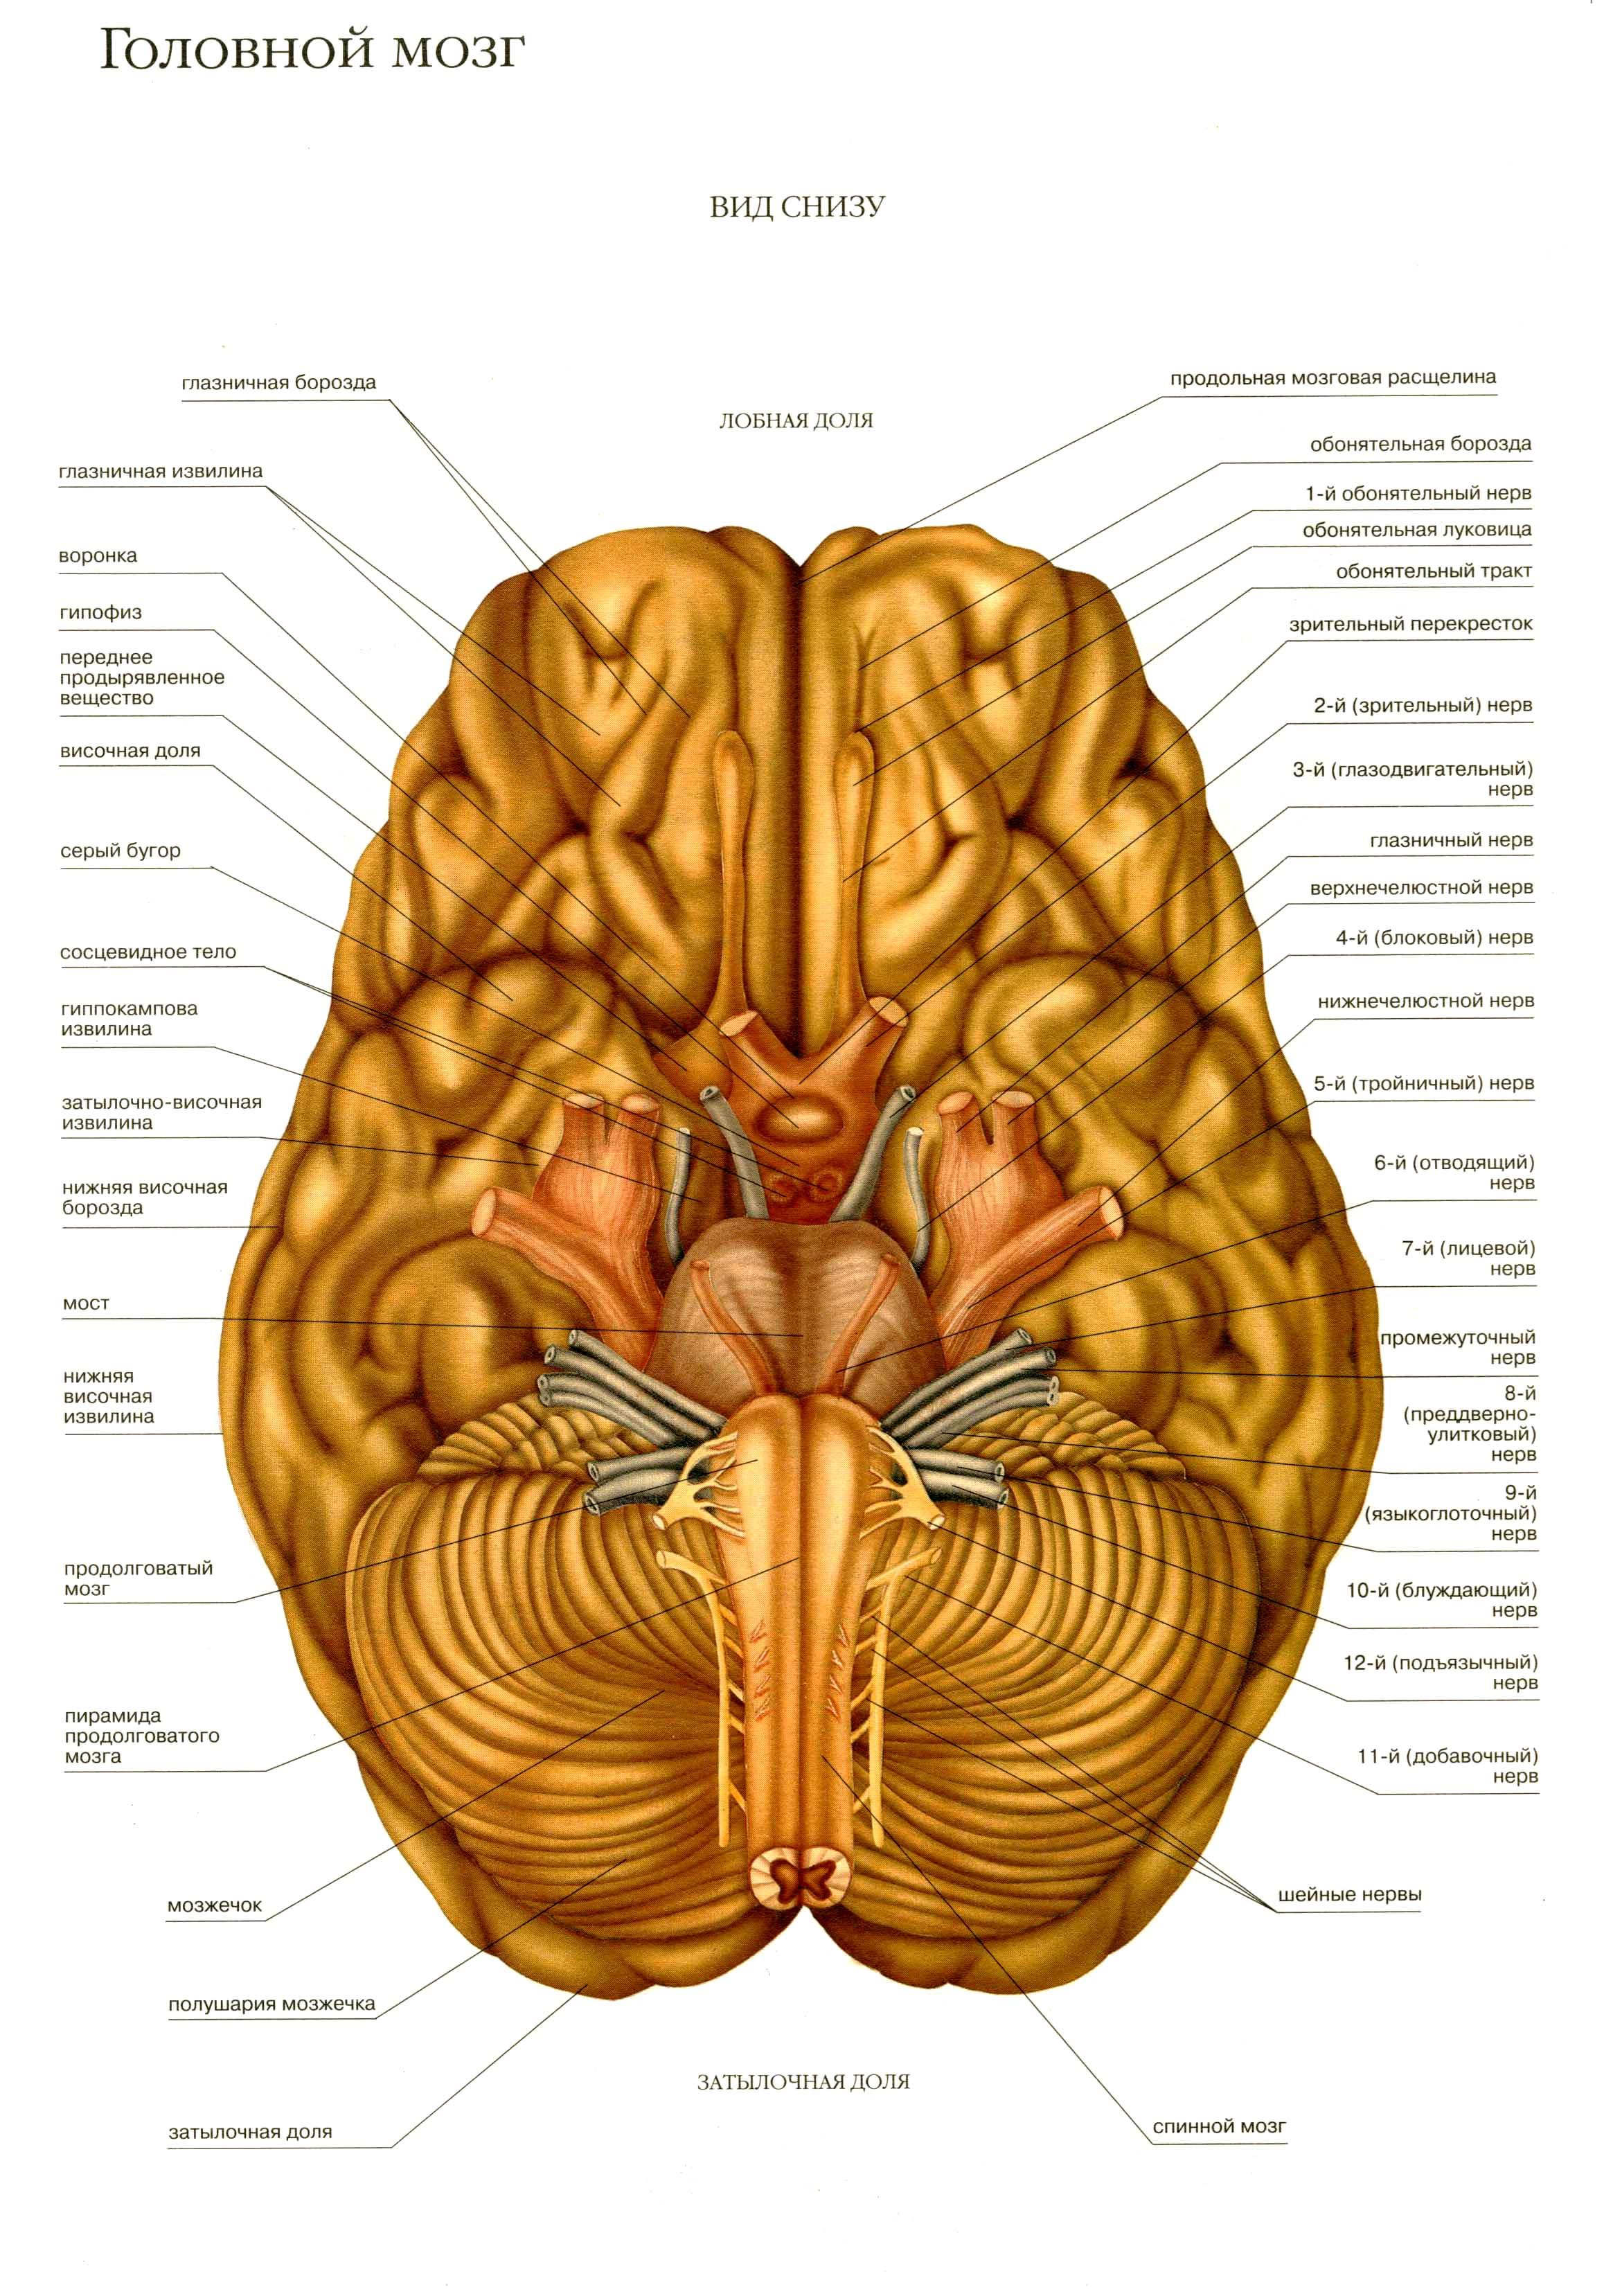

Анатомические снимки верхнелатеральной поверхности головного мозга